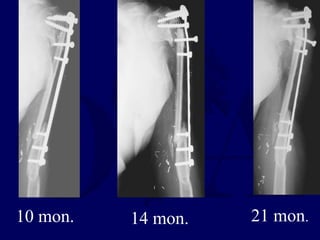

10 mon. 14 mon. 21 mon.

24 months post

injury

revision fixation

proximally with

bone graft

3 years post-

healed

uses hand for

ADLs